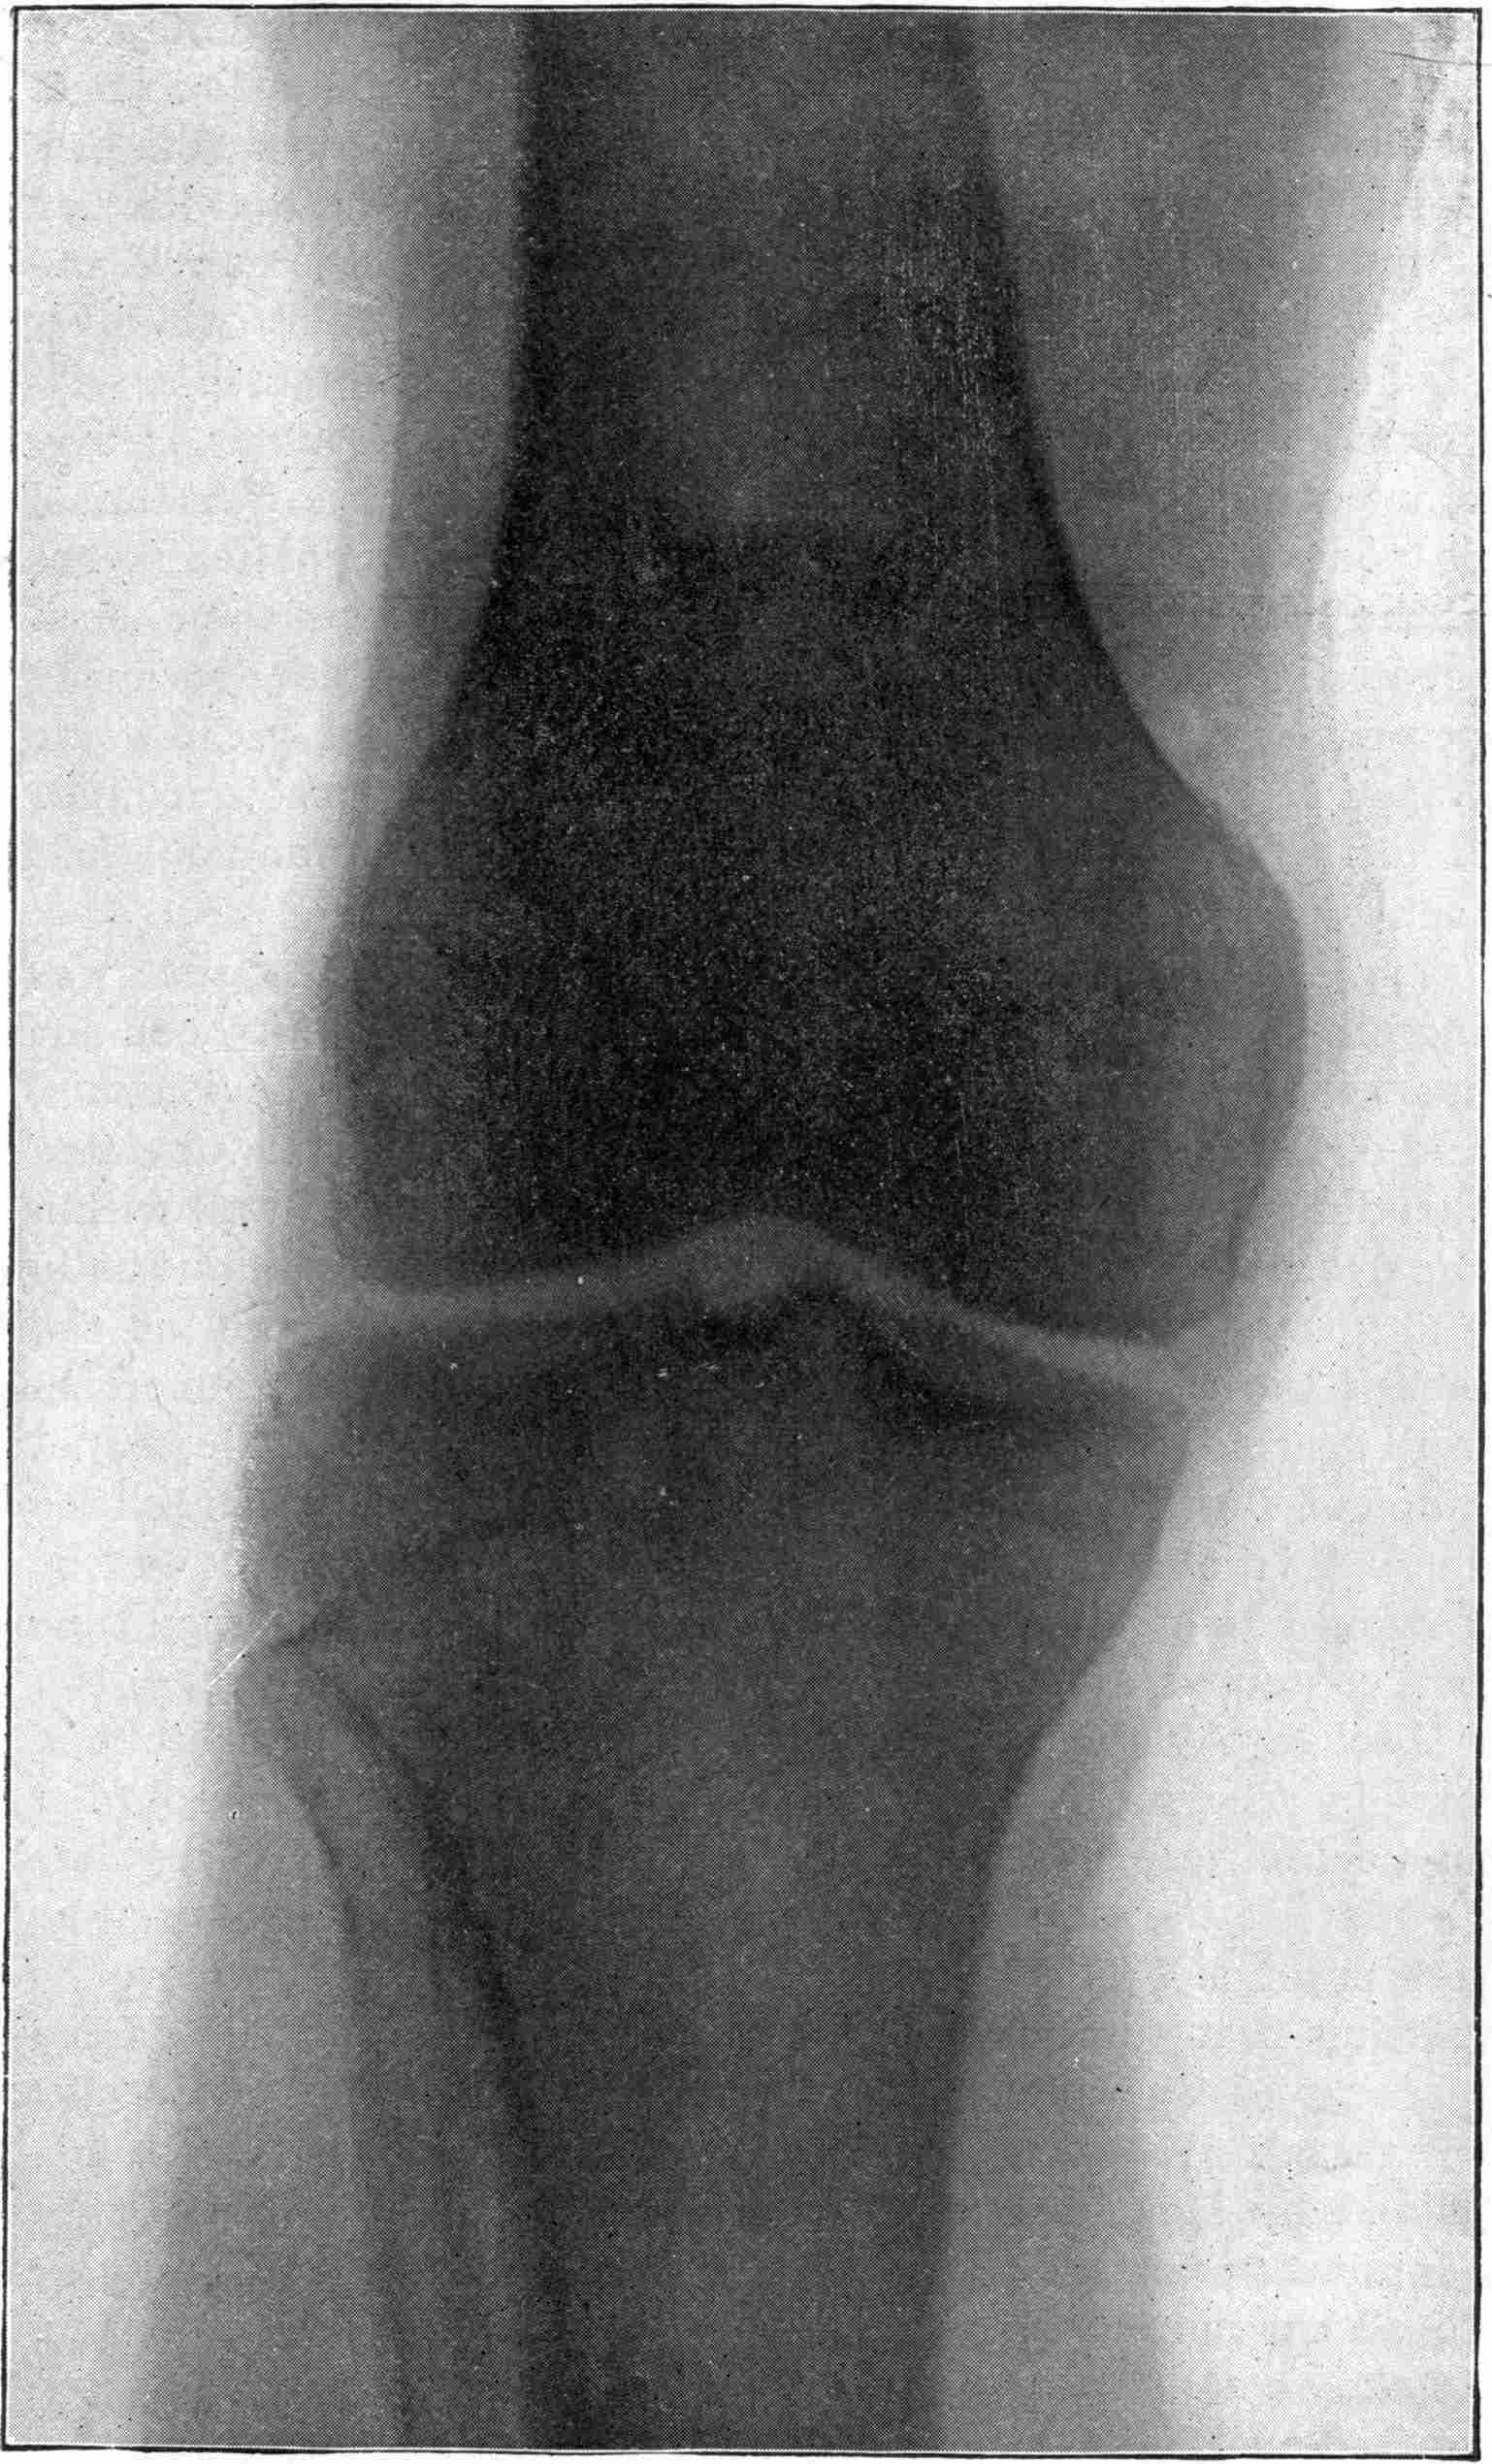

Fig. 1.—Head.

Fig. 2.—Broken Arm, Overlapping.

(Due to defective setting.)

Fig. 3.—Ribs.

Fig. 4.—Knee, Knickerbocker Buttons, Bullet in Femur.

FROM SCIAGRAPHS BY PROF. DAYTON C. MILLER. § 204.